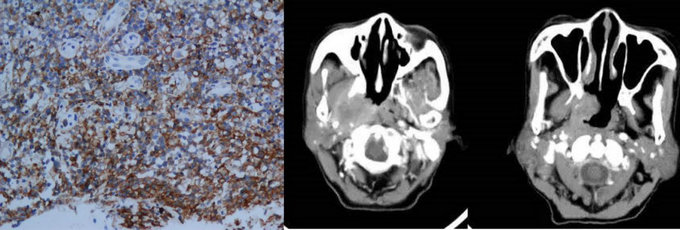

NK/T淋巴瘤病理及影像表現

據林桐榆教授介紹,CA分期納入了迄今為止最大樣本量的結外鼻型NK/T細胞淋巴瘤病例數,共有30家腫瘤中心的2153個病例納入研究,是目前世界上最大的NK/T淋巴瘤數據庫。研究發現相鄰骨質、皮膚和鼻旁竇侵犯、非鼻型病變或累及局部淋巴結等為 結外鼻型NK/T細胞淋巴瘤的獨立高危因素。據此,研究團隊構建了CA分期: